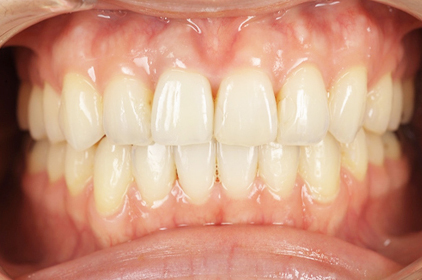

途中経過

患者様の主訴は、「保険の黄色くなったかぶせ物を白くしたい」でした。

保険のかぶせ物は、プラスティックで白い部分を作成するので、どうしても経年劣化で黄色く変色してきます。また、この患者さんは、横から見るとその歯がだいぶ前に出ていたために、少し出っ歯にも見えていました。

保険のかぶせ物を除去して、仮歯に置き換えて、その後プロビジョナルと言われる最終的な仮歯をセットして歯肉の状態を確認します。問題がないことを確認してから、最終的な型採り試適の後に最終的なセラミックのかぶせ物をセットしました。